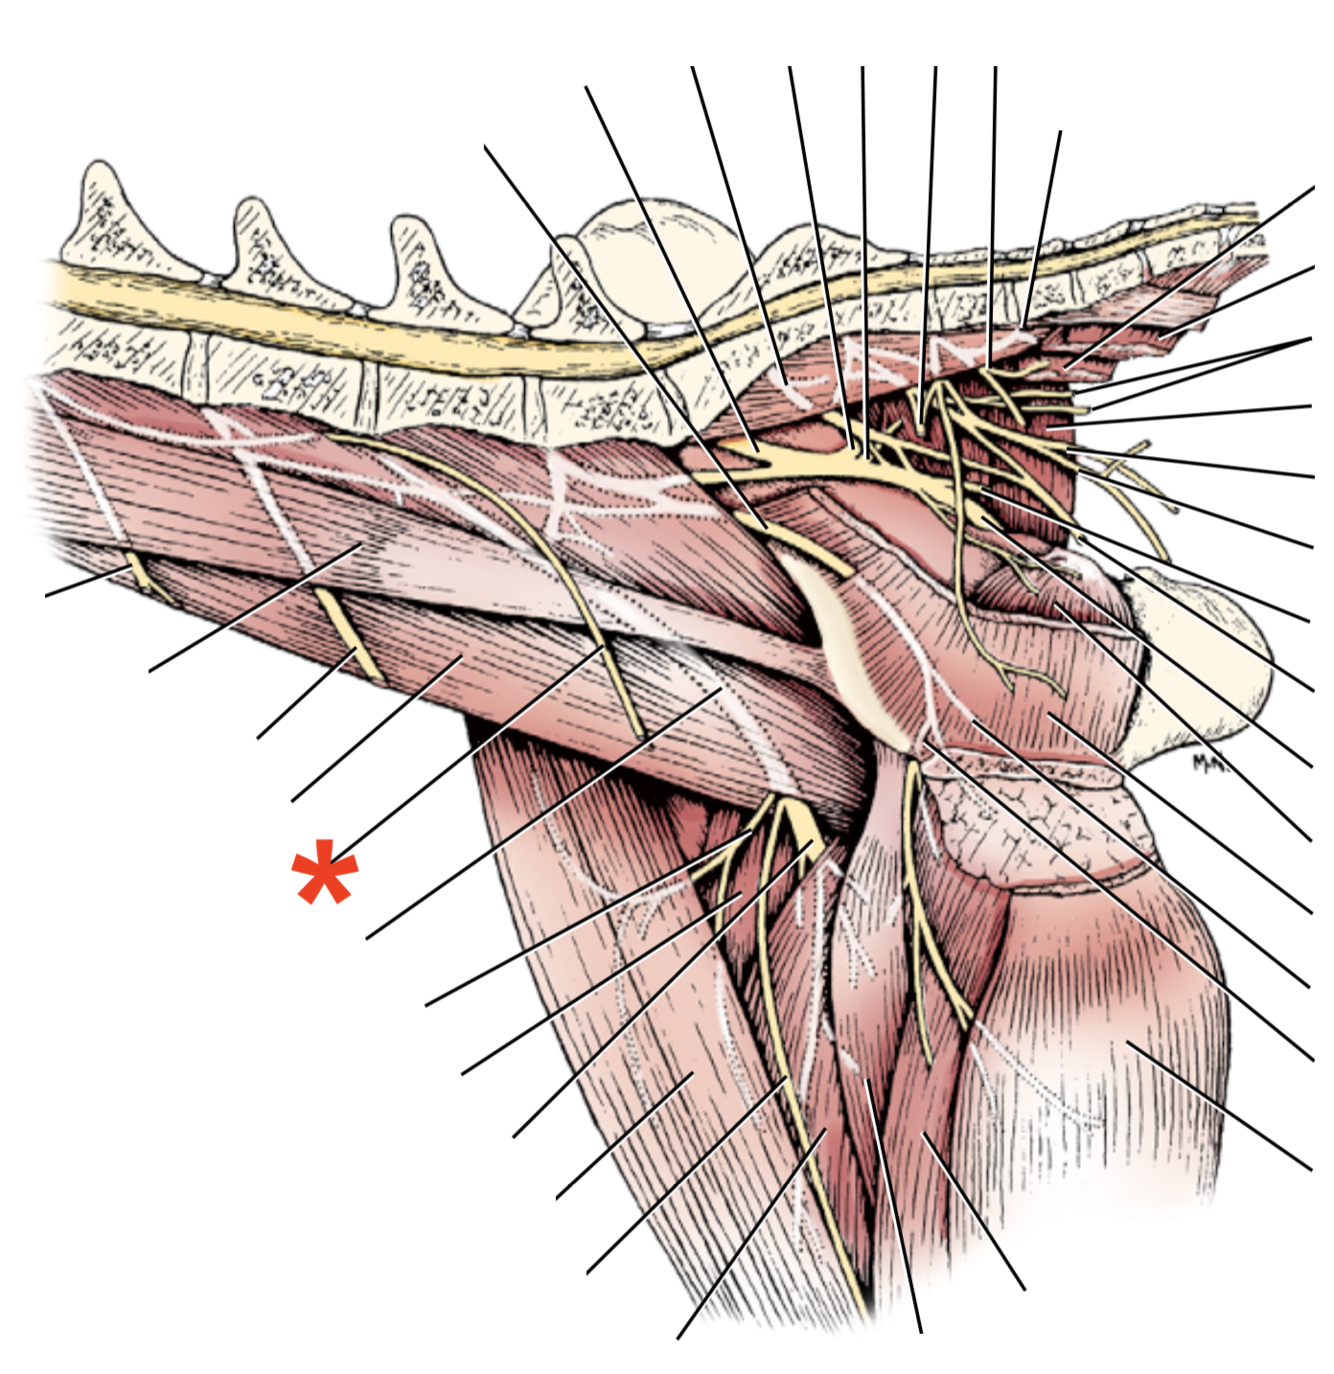

22

Q

A

N. genitofemoralis

- From L3-L4

- Branch Innervates m. obliquus internus abdominis

- Leaves abdomen through canalis inguinalis

- Branches:

- R. femoralis

- R. genitalis

23

Q

R. genitalis

A

- Supplies skin of pudendal region

- Innervates:

- M. cremasterica (male)

- Gl. mammaria inguinalis (female)

24

Q

R. femoralis innervation

A

Skin of proximal medial thigh

**Anulus inguinalis superficialis**

26

**M. obliquus internus abdominis**

27

**M. obliquus externus abdominis**